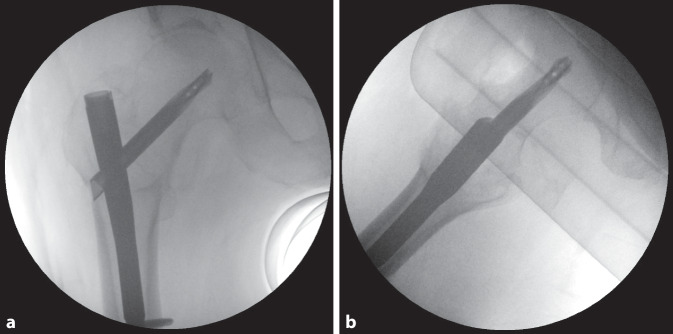

Es erfolgte die osteosynthetische Versorgung mittels dem an unserer Klinik zu jenem Zeitpunkt für diese Frakturen standardmäßig verwendeten proximalen Femurnagel, dem TFNA© (Fa. DePuy/Synthes, Zuchwil, Schweiz). Intraoperativ problemloser Ablauf mit annähernd anatomischer, geschlossener Reposition auf dem Extensionstisch sowie Fixation mittels TFNA© (130°, 170 mm Länge, 12 mm Durchmesser), bei leicht distaler und dorsaler Positionierung der Schenkelhalsklinge in den a.-p. bzw. axialen Bildverstärker(BV)-Aufnahmen (Abb. 2). Die Schenkelhals-Klingenspitze zeigte eine „tip apex distance“ (TAD) [8, 10] von 2–3 cm in den beiden BV-Ebenen. Das Einschlagen der Klinge erfolgte nach Aufbohren der lateralen Kortikalis mit dem entsprechenden Spiralbohrer, anschließend mit dem 2‑Stufen-Bohrer bis auf 85 mm, d. h. 10 mm kürzer als die gewählte 95 mm lange Spiralklinge. Der Führungsdraht lockerte sich nicht heraus; es fand keine Perforation ins Hüftgelenk statt. Anschließend erfolgten proximal die dynamische sowie distal die statische Verriegelung sowie der schichtweise Wundverschluss.